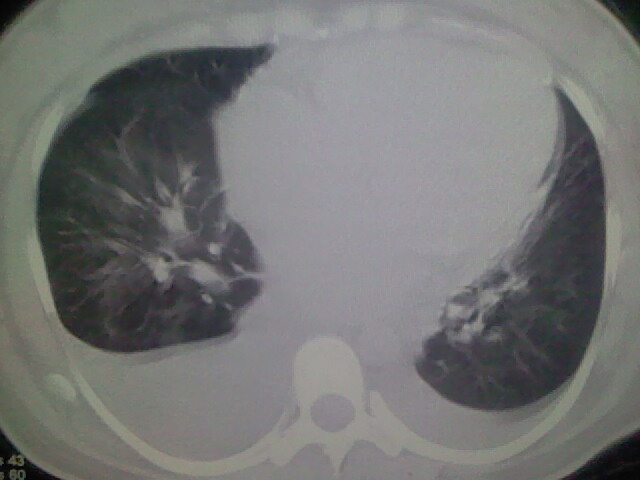

女,24,剖腹产后,突觉胸痛,干咳,不能平卧

双肺“肺泡性肺水肿” “胸腔积液”!

做个增强的 ct吧 pte(肺血栓栓塞)不能除外啊 在结合心电图 看看v1-v4导连的t波及st段改变。

患者允许的情况下建议进行心脏超声检查

临床资料及影象表现支持围产期扩张型心肌病改变,心衰。